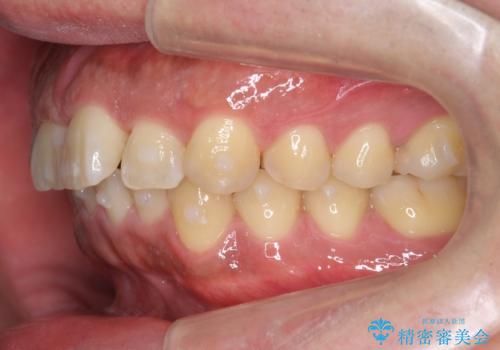

前歯のねじれを 1年かけずに矯正 インビザライン

- 前歯のねじれを主訴に来院。

インビザラインで治療しました。

前歯のねじれをセラミックで治そうとすると、抜髄といって、神経の治療が必要になる上、歯の幅も制限が出て理想的にはなりません。

保定の必要がありますが、天然歯を並べる矯正治療では、治療後の心配事が非常に少なく、保存的な処置となります。